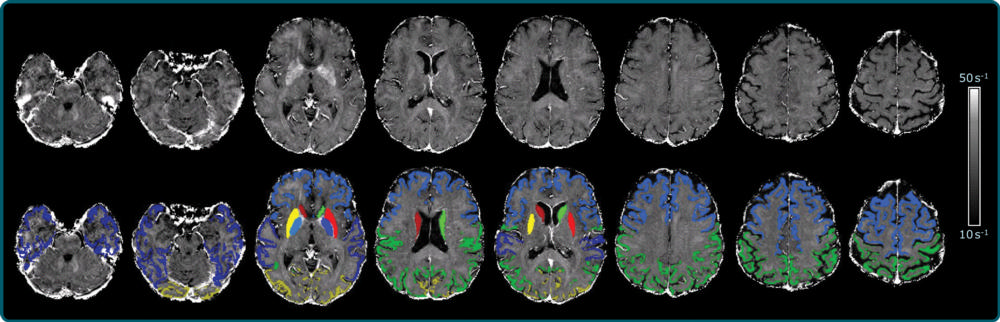

Figure 2. R2⁎ maps of healthy control participants and participants with Alzheimer disease. R2⁎ maps are windowed between 10 and 50 sec21. Differences in iron concentration in basal ganglia are too small to allow visual separation between patients with Alzheimer disease and control participants, and iron levels strongly depend on anatomic structure and subject age.

Figure 3. Schematic representation of MRI processing. Left: FreeSurfer-derived cortical and subcortical segmentations overlaid on a T1-weighted scan were affinely registered into R2⁎ space. Right: R2⁎ map corrected for macroscopic field inhomogeneities, where median R2⁎ values were calculated for each region and then used for further statistical analyses.